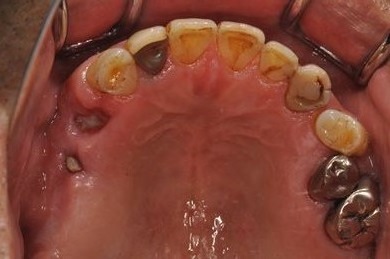

インプラントの症例写真 IMPLANT

骨再生インプラント治療+セラミック治療

| 性別/年齢 | 男性 / 60歳 | ||||||||||||||||||||||||||||||||

| 主訴 | 右上奥歯が動いて痛みがある。 | ||||||||||||||||||||||||||||||||

| 治療方針 | サイナスリフトにて上顎洞を拳上し、骨再生療法を用いてインプラント治療を可能にする。 | ||||||||||||||||||||||||||||||||

| 治療内容 | インプラント5本(サイナスリフト、GBR)、ハイブリッドセラミッククラウン5本、メタルボンドセラミッククラウン1本(メタルボンド用土台1本)、ハイブリッドセラミックインレー、遊離歯肉移植手術 | ||||||||||||||||||||||||||||||||